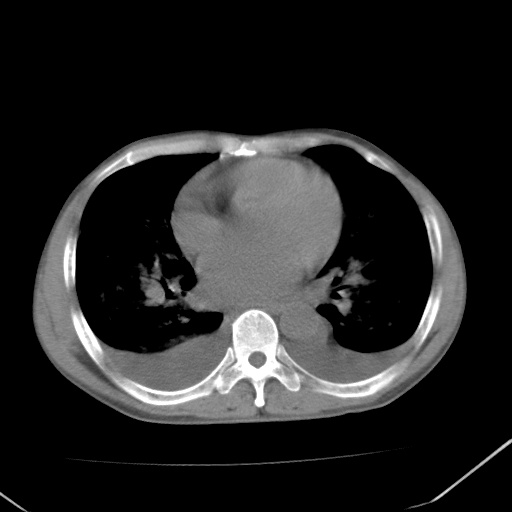

双肺野对称性磨玻璃影,分布于内中带,双侧胸水,患者有咯血。

左心房增大,考虑心衰,肺水肿。

双肺野广泛对称性磨玻璃影、实变影,以肺门为中心,主要分布于内中带,符合典型肺泡性肺水肿;伴双侧胸腔少量游离积液。结合患者既往病史且咯血就诊,支持多因素(尿毒症等)所致之肺水肿、肺出血、胸水;影像表现暂不考虑心源性水肿,且症状也不太符。需密切随诊结合临床治疗等进一步明确。

心影增大密度略低,双肺磨玻璃样高密度影及双侧胸腔积液,考虑心功能不全继发双肺肺水肿及双侧胸腔积液。心影密度略低,考虑贫血所致。

双肺堆成磨玻璃影,双测胸腔积液。考虑:肺水肿、间质性肺炎、真菌感染、ards、hiv感染、肺出血。